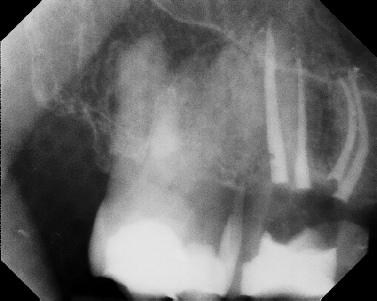

COMPLICATED ANATOMY LARGE LESIONS CALCIFIED CANALS PERFORATION / RESORPTION SEPARATED INSTRUMENTS SURGICAL CASES RETREATMENT / pOST REMOVAL OPEN APICES ACCESS THRU CROWNS Root Canal Case Portfolio

Pre-op Post-op 1 Post-op 2